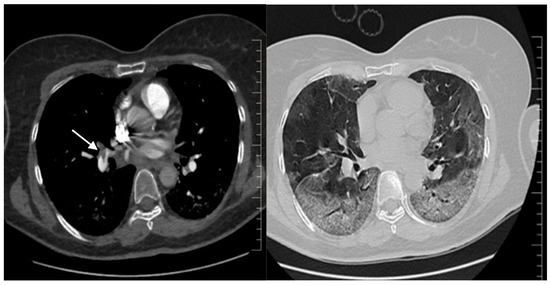

2. Case Report